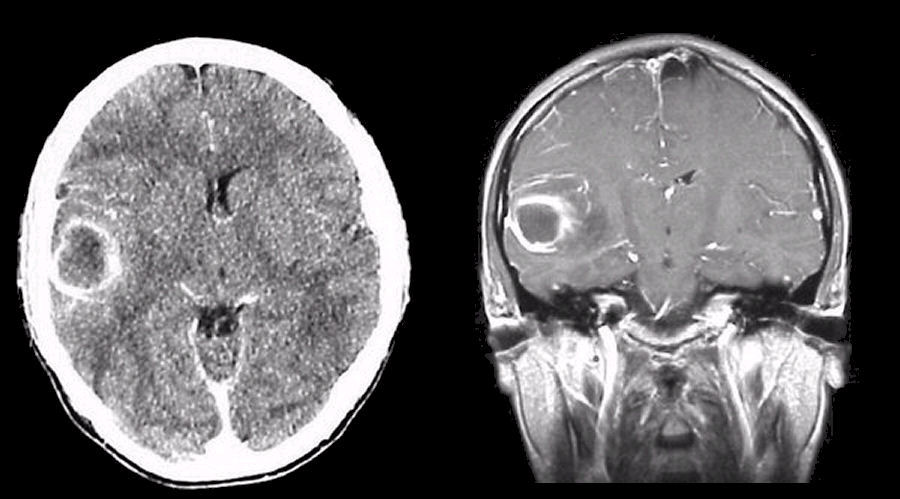

| Brain abscess | Ring-enhancing lesion with surrounding oedema; often appears as a mass lesion with central low attenuation. MRI and clinical context help distinguish from tumour. |